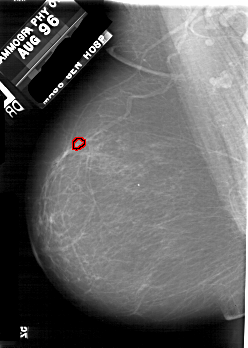

A_1731_1.LEFT_CC

LEFT_CC LINES 5311 PIXELS_PER_LINE 3691 BITS_PER_PIXEL 12 RESOLUTION 43.5 OVERLAY

FILE: A_1731_1.LEFT_CC.OVERLAY

TOTAL_ABNORMALITIES 1

ABNORMALITY 1

LESION_TYPE CALCIFICATION TYPE PLEOMORPHIC DISTRIBUTION CLUSTERED

ASSESSMENT 4

SUBTLETY 2

PATHOLOGY MALIGNANT

TOTAL_OUTLINES 1

BOUNDARY